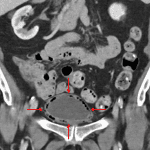

Indication: Lower abdominal pain

Findings

- Diffuse bladder wall thickening with intramural gas and perivesical fat stranding

- Emphysematous cystitis

Findings are concerning for emphysematous cystitis.